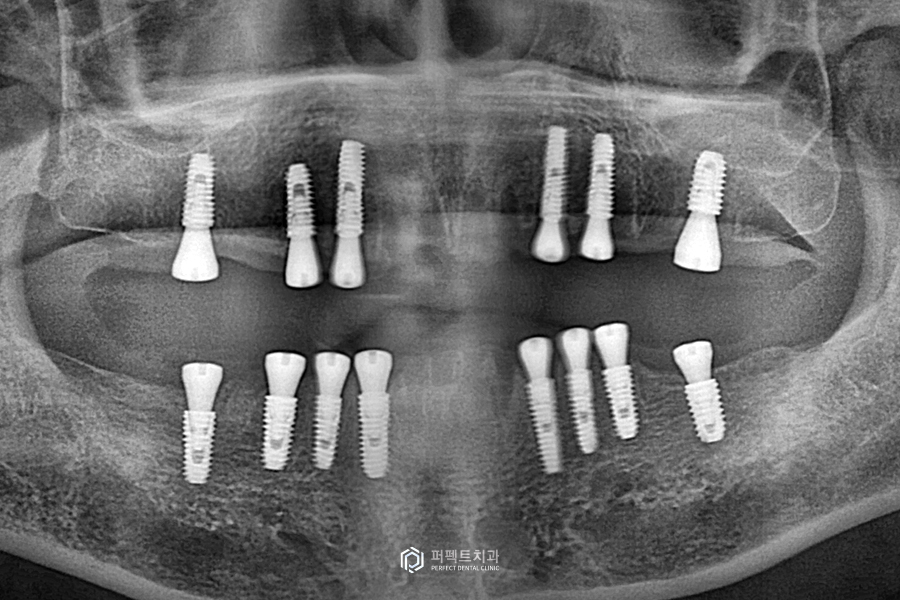

그럼 우선 임플란트 식립 후의 모습을 확인해 보겠습니다.

전체 치아를 발치하여 본인의 치아가 하나도 남아있지 않은 상태에서 임플란트를 심어놓은 경우입니다. 윗니 6개, 아랫니 8개를 식립했는데, 전악 임플란트 즉 전체 임플란트를 할 때에는 최소 6개가 심어져 있는 것이 좋고 혹은 8~10개 정도 심어져 있으면 좋습니다.

나머지 치아들은 다 걸어서 만들어지기 때문에 당연히 치아를 걸 수 있는 뿌리가 더 많으면 지지하는 힘이 커지니까 더 좋을 수밖에 없습니다.

임플란트 수술은 두 번에 걸쳐서 간단하게 끝냈고, 또 하나는 위 환자 분의 경우 요즘 많이 진행하고 있는 네비게이션 임플란트를 진행하였습니다. 네비게이션 임플란트란 가이드를 만들어 위치를 잡고 정확한 자리에 임플란트를 심는 방법이라고 생각하시면 됩니다.